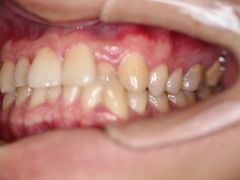

• -德伦口腔

LEE | 19-05-21

报错